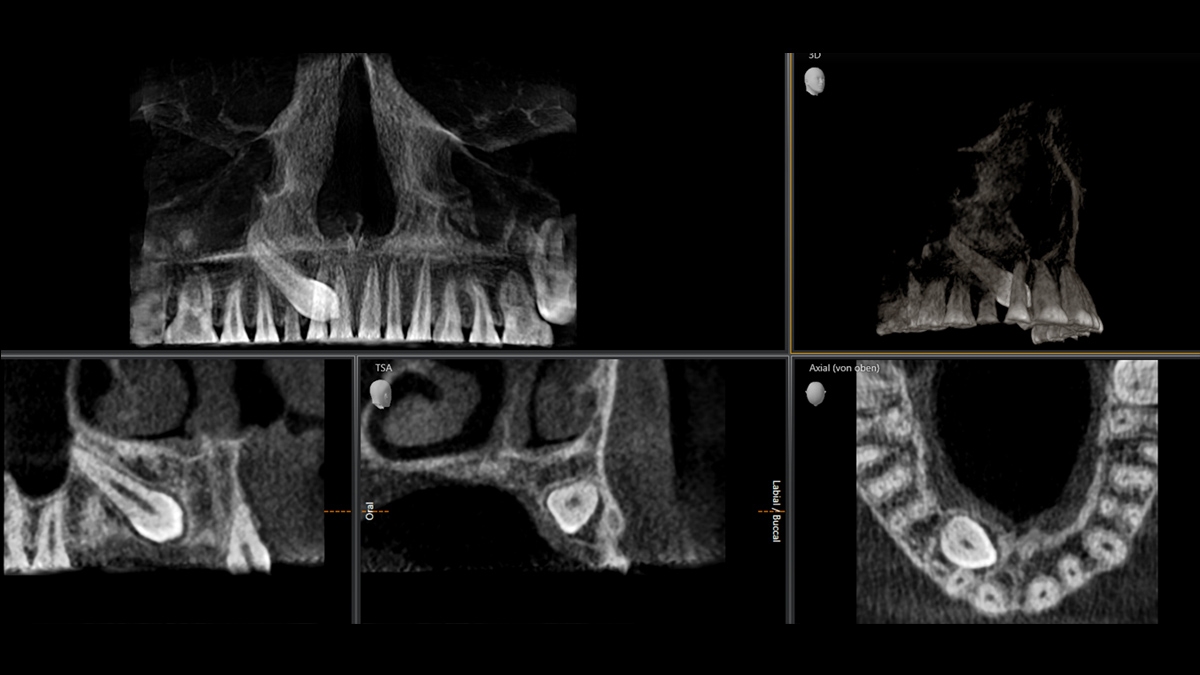

Exemplary 3D Images

Volume Ø 5 cm x 5.5 cm HD

3D Low Dose Indication Examples

Indication: Determining the position of teeth. CBCT Volume: Ø 8 cm x 8 cm at 8 μSv

Indication: Locating displaced canine teeth. CBCT Volume: Ø 5 cm x 5,5 cm at 3 μSv